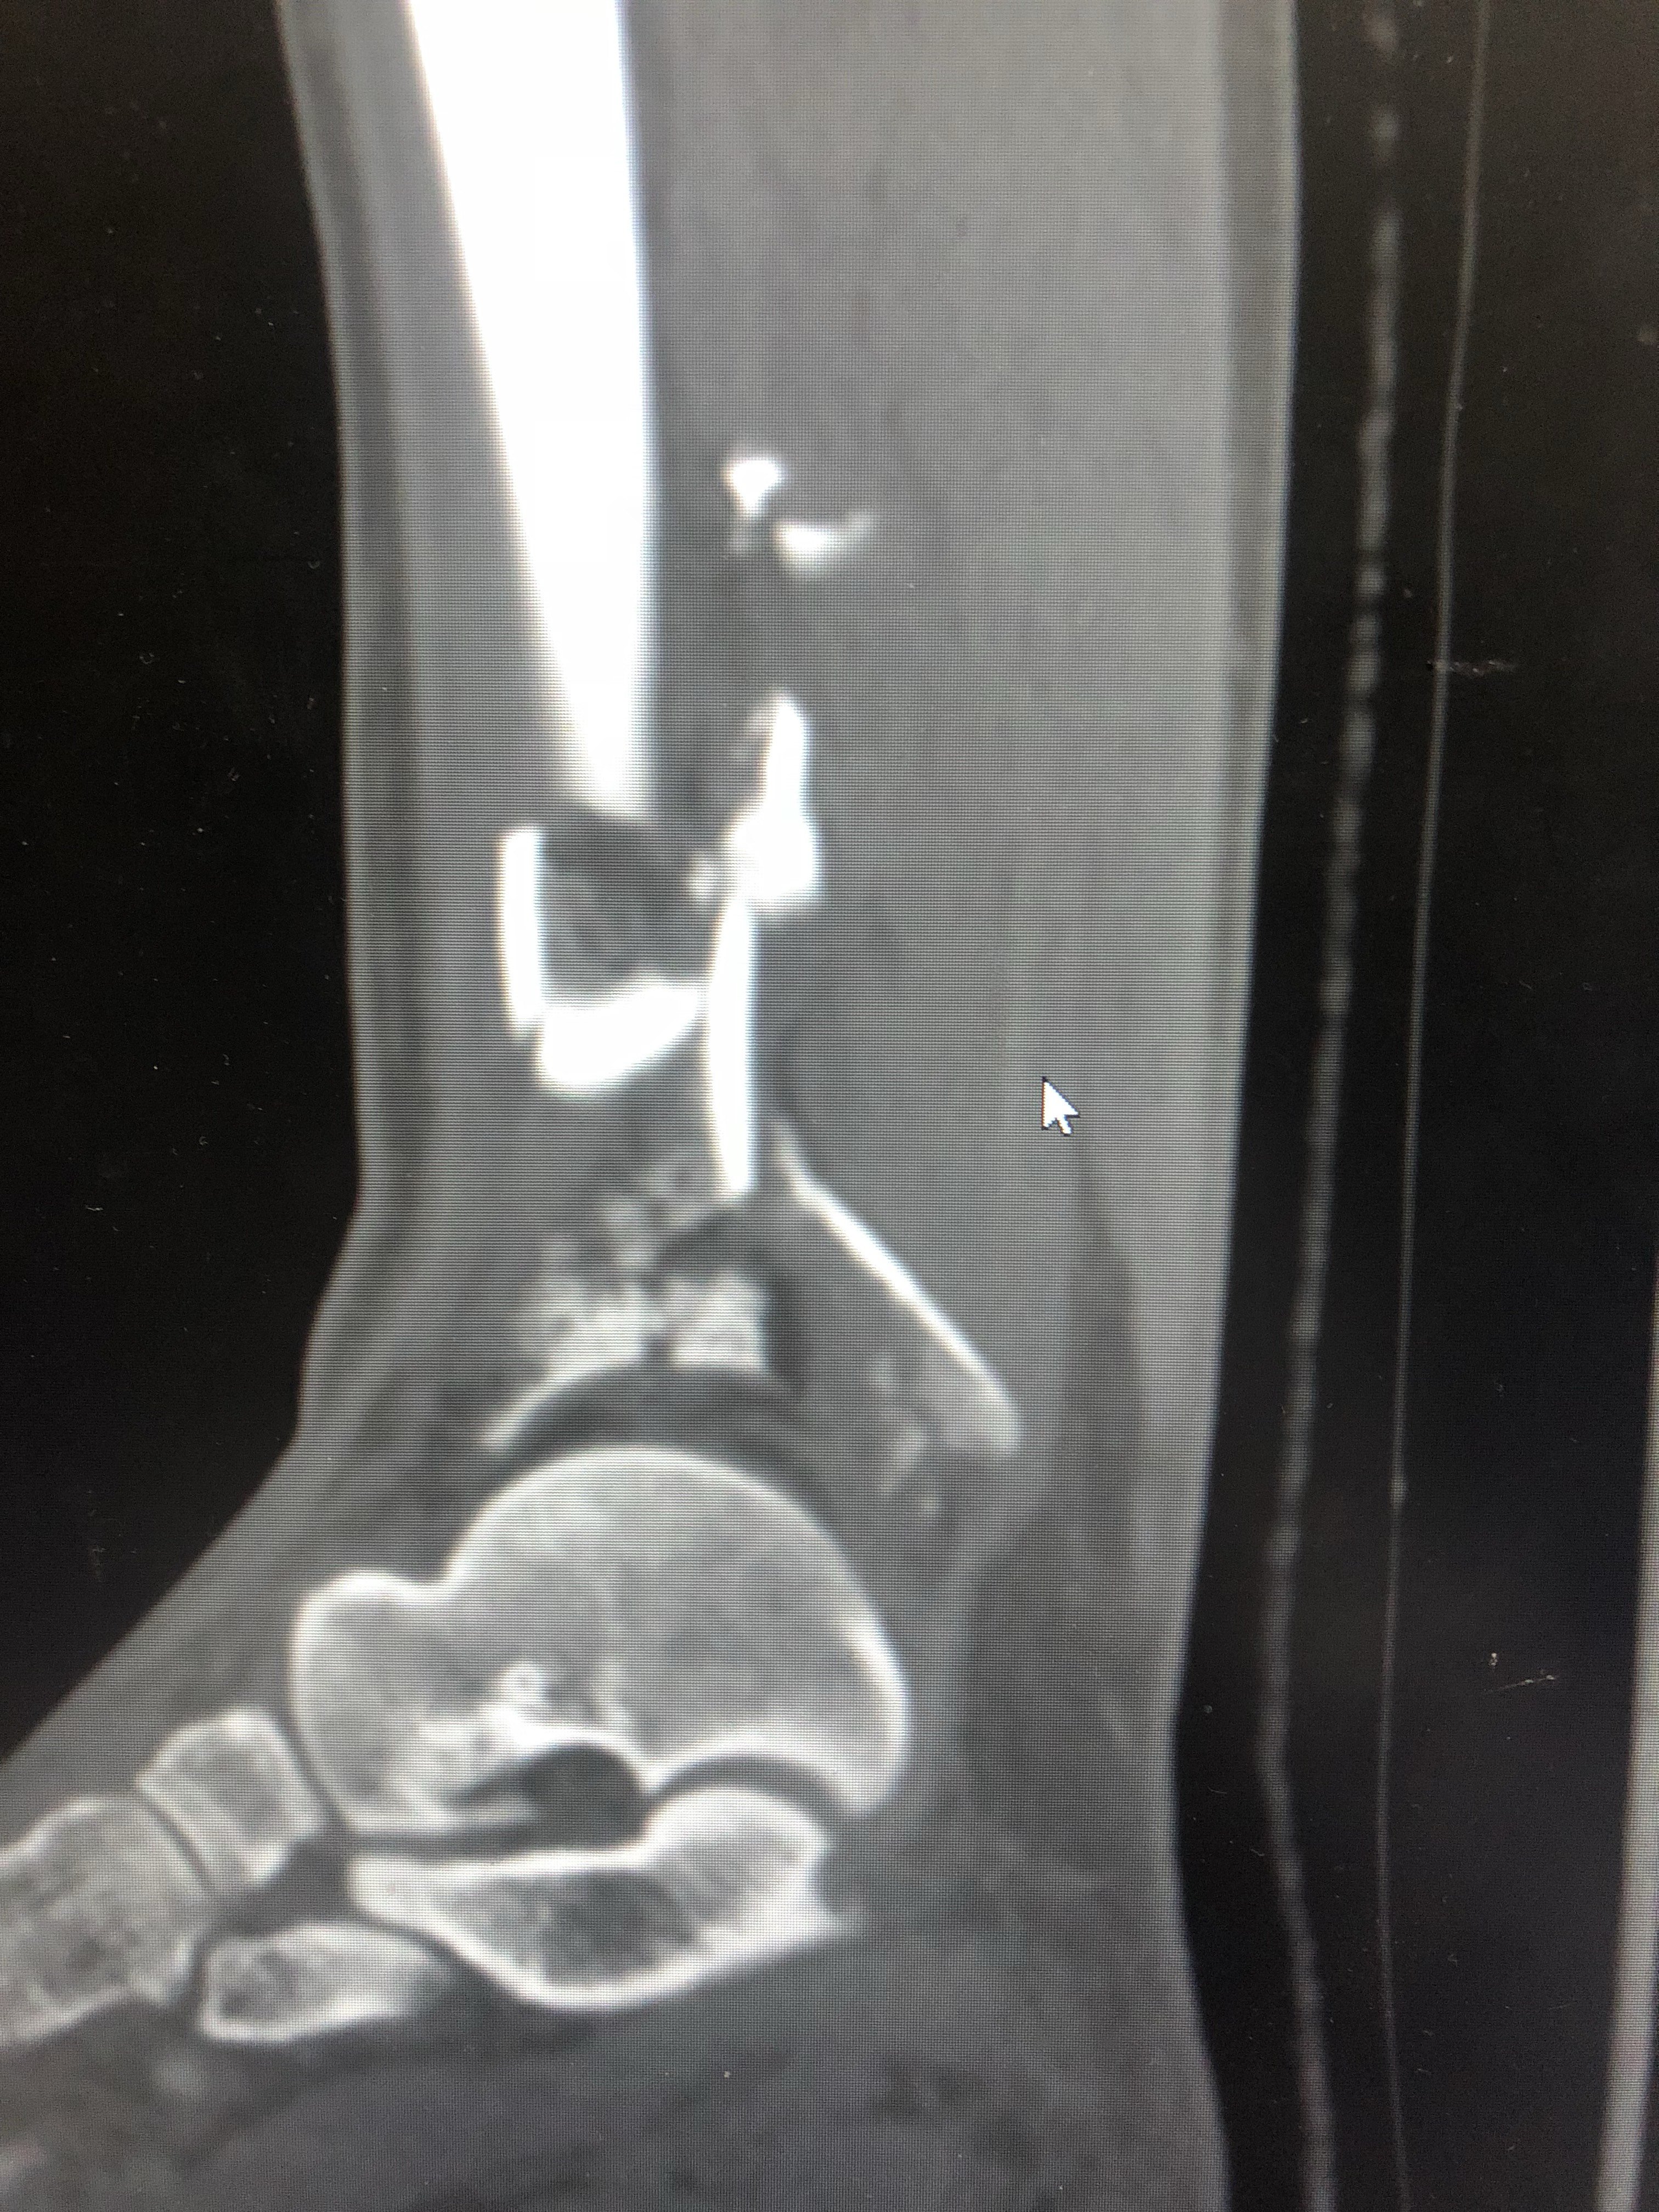

受傷した 画像所見より左腓骨遠位端骨折と診断された前 脛腓靭帯付着部の剥離骨折, 腓骨のらせん骨折および脛骨後 果の骨折からLaugeHansen分類ではSER型stageⅢであった 受傷後9日目にロッキングプレートを用いた骨接合術が施行 された左足首の骨折。 過去に足首を捻挫または骨折をして、治ってからも予防のためにサポーターを着用していませんか? サポーターを着用していると捻挫の予防になるかもしれません。しかし、時に逆効果になってしまう場合もあります。 &n交通事故の被害に遭い、脛骨骨折や腓骨骨折の怪我を。 その後、もしも後遺症が残ってしまったとしたら。 これからも長く続く治療やリハビリの生活では、 脛骨骨折・腓骨骨折から回復するために支払う治療費 怪我をしたことや後遺症が残ったことによる精神的苦痛に対する慰謝料 将来

一例严重的胫腓骨远端粉碎骨折